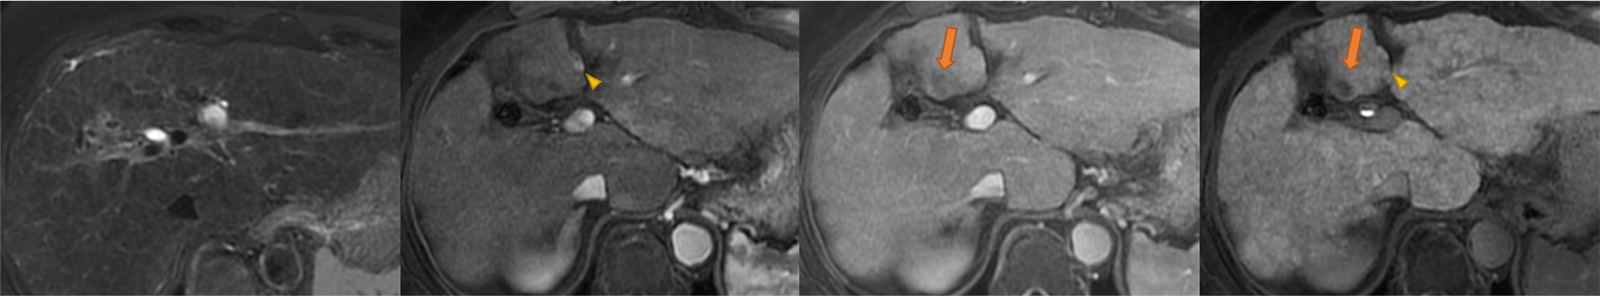

図2.26ヶ月後のEOB-MRI画像(左から脂肪抑制T2強調画像、動脈相、門脈相、肝細胞相)

S4病変には増大が見られ、門脈相でのwashoutが観察されるようになっている(矢印)。早期濃染は明らかではなく、T2WIでも周囲肝実質と等信号を示す。同じくS4に肝細胞相で低信号を示し、早期濃染を伴う病変が出現している(矢頭)。